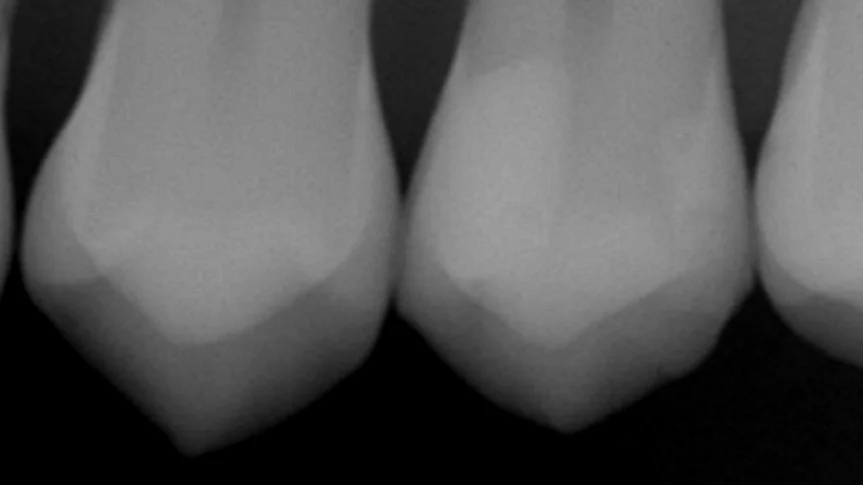

この時に詰めた歯のレントゲンがこちらですね。

画面右側の歯がそれになります。

1年程度では一才の段差がない状態をキープできていますね。

内面にもCは特に発生しておらず、状態としては非常に良好であると考えられます。